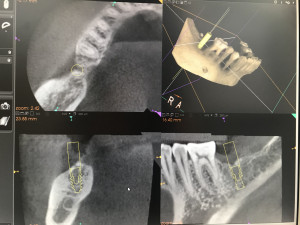

このインプラント治療をする前に特殊なレントゲン撮影(歯科用CT)で徹底的に骨の形を分析して、正しいインプラント埋入位置を計画します。

治療計画したインプラント埋入位置をデータ化してそれを3Ⅾプリンターに送るのです。このデータと、実際の口の中のデータ(現在は歯型模型)をPC上で融合させるのです。そうするとサージカルステントといってインプラント手術用の重要な道具を作ることが出来ます。いわばこれは「物差し」です。